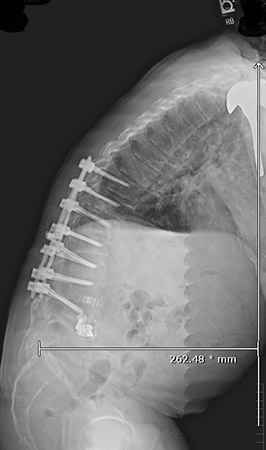

Williams met with Cyrus Wong, M.D., a neurosurgeon on the medical staff at Texas Health Fort Worth and North Texas Neurosurgical & Spine Center, a Texas Health Physicians Group practice. “Michael’s center of gravity was completely off, causing him to lean forward by more than 10 inches every time he attempted to stand or walk,” Wong said.

After undergoing several diagnostic studies, including MRI and CT scans, along with physical exams Williams was diagnosed with scoliosis – a sideways curving of the spine – and flatback syndrome, a condition where the lower portion of the spine loses its normal curvature. “When you have flatback syndrome, you’re in constant pain and disability, you have difficulty standing up or looking straight, and your daily activities are hindered or simply become non-existent,” Wong explained.

Williams underwent pedicle subtraction osteotomy, a complicated surgical procedure that allows a neurosurgeon to strategically reshape the vertebrae to realign a deformed spine. After his spinal procedure, Williams was cared for at Texas Health Fort Worth. “The day after surgery, a nurse came to my room and said I needed to start walking. I told her she’d lost her mind,” Williams said. “Eventually, I got out of bed, but I didn’t feel any pain. I walked up and down the hallways near my room, and I didn’t want to stop.”